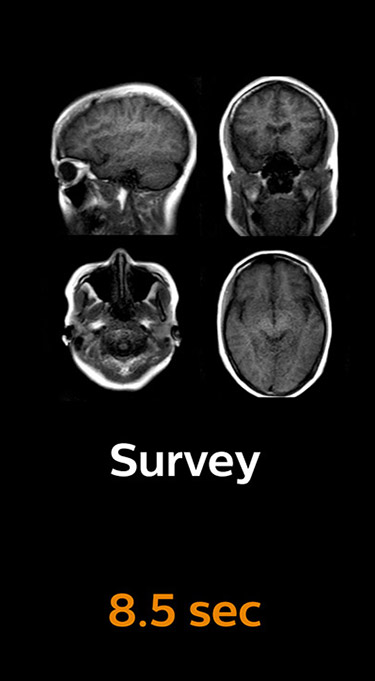

Fast MRI of brain

With Compressed SENSE, the scan time for the routine brain examination at KNC was reduced from 15:48 to 10:19 minutes, which corresponds to 35% reduction.

Brain without Compressed SENSE

Brain with Compressed SENSE

Ingenia 3.0T CX

Scan time 15:48 min.

Scan time 10:19 min.